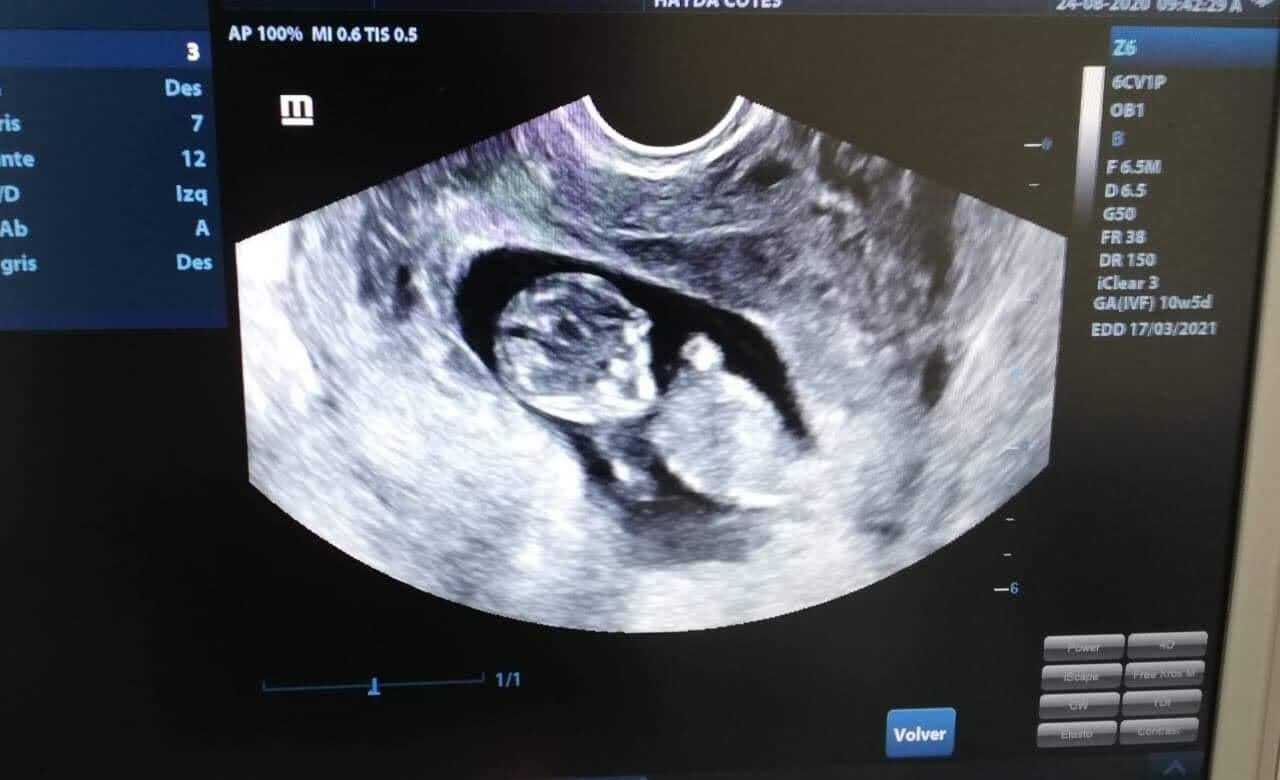

ULTRASON